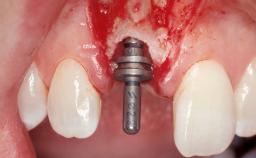

Immediate Placement of an Implant in a Maxillary Left Central Incisor Site

| Bone Augmentation | Horizontal|Simultaneous |

| Augmentation Materials | Xenogenous|Membrane |

| Soft Tissue Grafting | Simultaneous |

| Placement Protocol | Immediate implant placement |

| Risk of Complications | High |